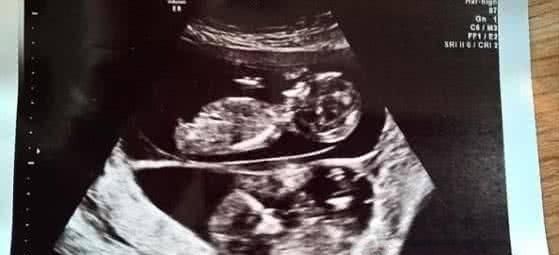

【 异期|女子怀孕五个月后再度怀孕,医生检查过后,丈夫顿感泣不成声】在美国阿肯色州,一名孕妇在怀孕五个月后例行超声波检查时令医生大吃一惊,因为医生们发现该名孕妇在腹中的女婴旁边,再怀有一名胎龄更小的男婴。

据社交媒体报道,阿肯色州KFSM-TV电视台接获的声明指出,相信格罗文伯格太太是在怀有女婴吉莉恩整整五个月后才怀有男婴赫德森的。

这一种古怪的表象叫异期复孕,就是孕妇在已经怀孕后卵巢又开释了一颗卵子。第二颗卵子也受精了,然后就一起怀上了两个宝宝。